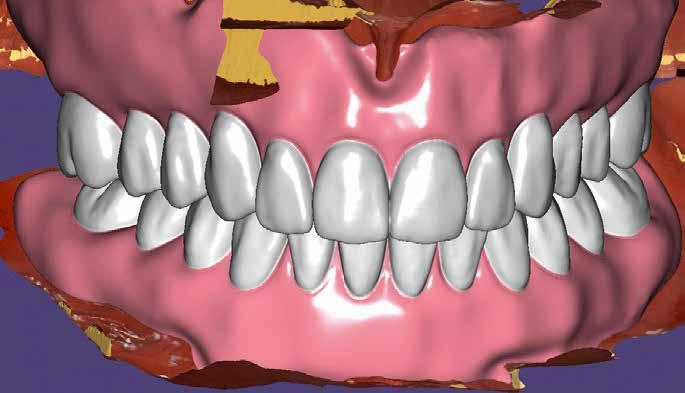

A digitális lenyomatvétel

A kezdetben említettük, célunk a digitális technológiák maximális kihasználása volt. Fontos volt számunkra, hogy semmilyen minőségi kompromisszumba ne kelljen bocsátkozni. A digitális lenyomatvétel a Kulzer cég cara i700-as intraorális szkennerével történt (4. kép). Mint számos ma használatos készülék, ez is egy optikai rendszer, amely minden, a kezelőorvos számára is látható területet beolvas. Akárcsak az analóg eljárásban, itt is szükséges a szulkusztágító fona-

6. kép: A felső állcsont digitalizálása a csontos szájpadnak köszönhetően sokkal egyszerűbb, mint az alsóé.

lak használata, hogy precízen felmérhető legyen a preparációs határ (5. kép). Az optikai beolvasás miatt a kezelőcsapat tudatában kell legyen annak, hogy a nyálkahártya rezilienciája nem lesz figyelembe véve. Ezt a fontos információt a későbbiekben, a mock-up készítése során kell rögzíteni. Általánosságban kijelenthető, hogy a felső állcsont optikai beolvasása problémamentesebb, mint az állkapocsé. A bemutatott esetben különösen az erősen sorvadt gerinc és a szublingvális szájfenék jelentett kihívást, hiszen minél több alsó állcsontot kellett lemintázni. A cara i700-sal a felhasználó lehetőséget kap kiegészítő információként az ideiglenes pótlás bazális felszínének beolvasására, és ennek öszszevetésére a szájképletekkel. Csak ezen az úton lehetséges akceptálható lenyomatot készíteni (6–8. képek).

7. kép: Az alsó állcsont a becsavarozott digitális lenyomatvételi fejekkel.

8. kép: Az ideiglenes bazális részének összehasonlításával a szájfenék könnyebben meghatározható.

A digitális intraorális munkamenet előnye, hogy a kezelőorvos közvetlenül beolvasás után bekapcsolhatja a fogtechnikai labort a munkába, megtárgyalandó a preparációt és a beolvasás minőségét. A továbbiakban az adatállomány (a preparáció és az ideiglenes felszínének kialakítása) átküldhető a laborba. Ebben az esetben az ideiglenes (9–10. képek) beszkennelésén kívül analóg harapásregisztrátum is készült a beartikuláláshoz.